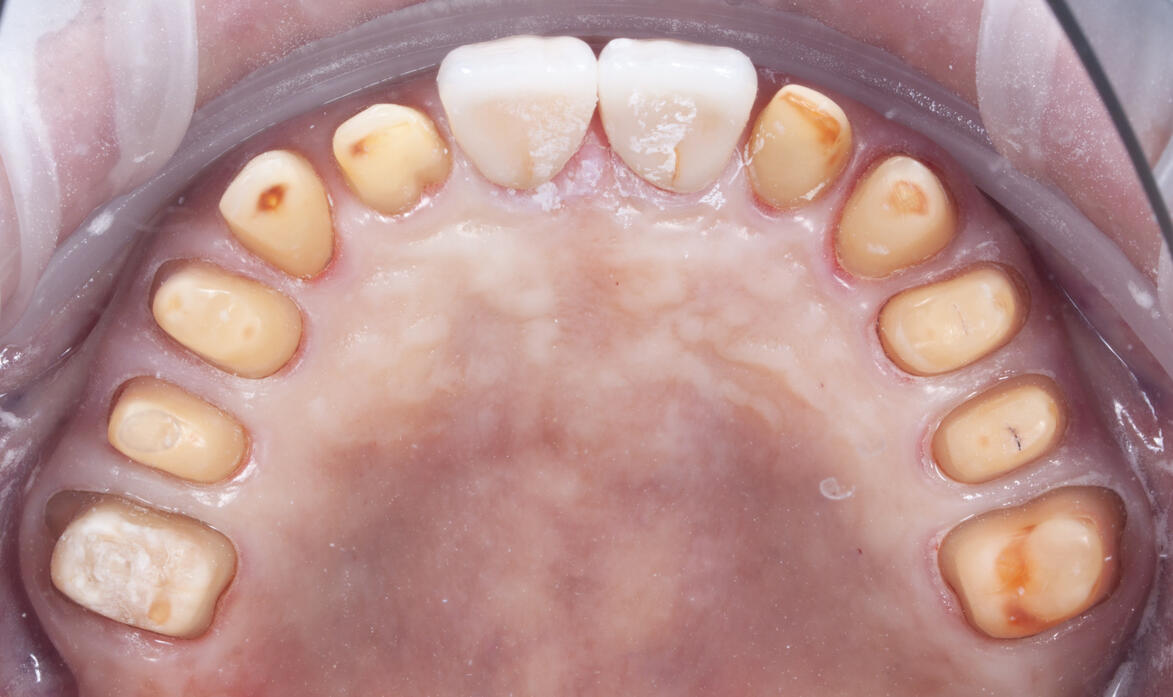

obecné zásady preparace pilířového zubu

základy plánování, volba materiálu a práce s ním od preparace po fixaci

základy estetického plánování

prezentace úspěšných i neúspěšných případů